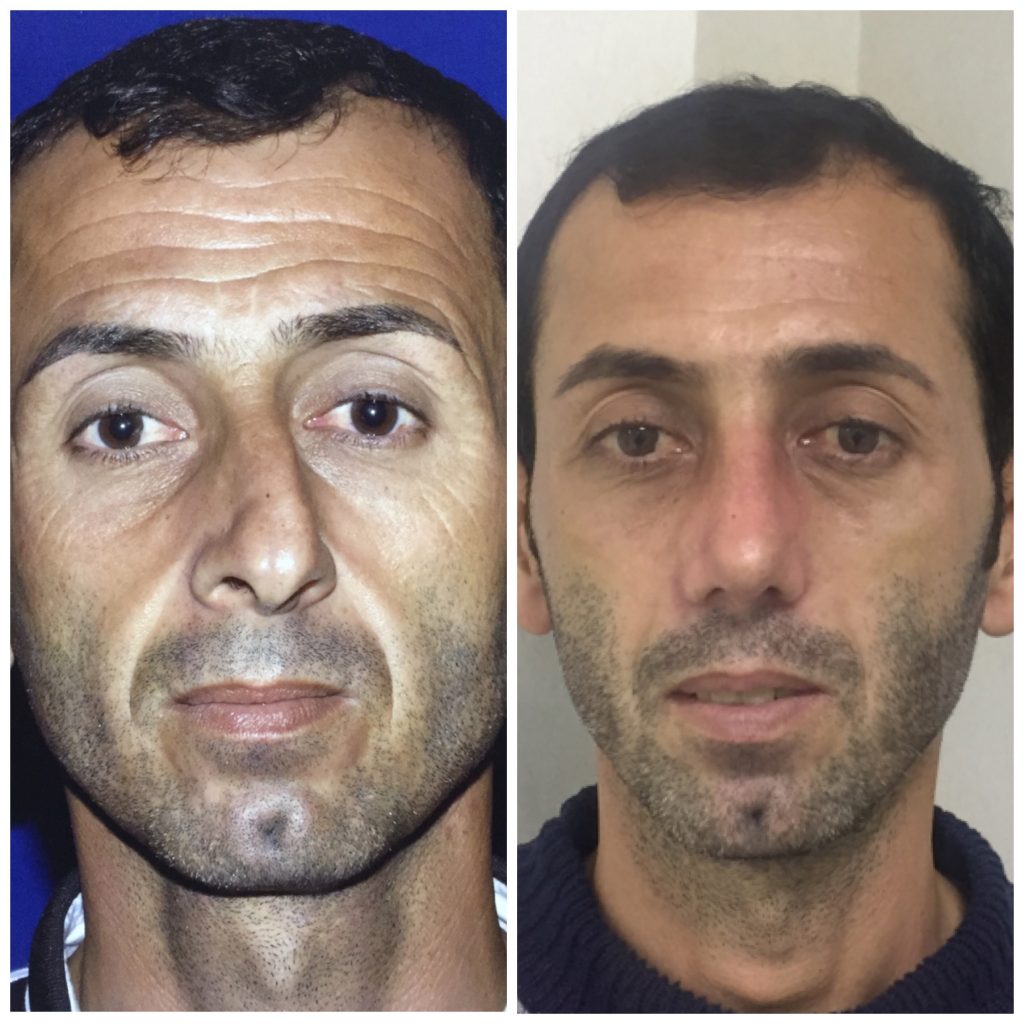

دکتر عیسی عبدی در رشت

دکتر عیسی عبدی در رشت

– متخصص جراحی فک , پلاستیک صورت و بینی

دکتر عیسی عبدی در رشت

جراحی فک , پلاستیک , صورت وبینی

جراحی ترمیمی و زیبایی فک و صورت و جمجمه و گردن